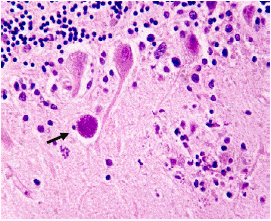

A pesar del tratamiento, la paciente evolucionó rápidamente a una falla orgánica múltiple y falleció a los diez días del ingreso. Se hizo la autopsia y en el estudio histopatológico de tejido miocárdico, cerebral y de músculo esquelético, se encontraron quistes tisulares con formas sugestivas de bradizoítos de Toxoplasma gondii (figura 3 4, 5 6, 7). Estos se sometieron al estudio de inmunohistoquímica utilizando el anticuerpo monoclonal específico para la proteína de membrana P30 de T. gondii (Novocastra™, clon TP3), purificado a partir de líquido ascítico de ratón y diluido en una solución tampón de fosfato salino (PBS), pH 7,6, con albúmina de suero bovino (BSA) al 1 % y 0,09 % de azida de sodio, cuyo resultado confirmó la presencia del parásito en los tejidos evaluados (figuras 8-9-10).

Figura 7 Corte histopatológico de cerebelo con quiste que contiene formas sugestivas de bradizoítos (flecha). Hematoxilina y eosina, 40X.